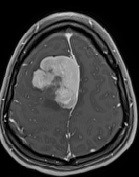

MRI image of brain tumourDr. John Woulfe and his colleagues have identified a new kind of brain tumour. It was removed during a young woman's treatment, and did not match any existing tumour classifications. The team found that the tumour expressed a never-before-seen fusion gene, made up of the MN1 gene fused to the KMT2A gene. Fusion genes can contribute to cancer by disrupting the regulation of cell growth and death, although more research is needed on this particular fusion gene. "We hope researchers and healthcare providers will keep an eye out for this kind of tumour," said Dr. Woulfe. "The more examples we can find, the better we will be able to understand how the tumours behave and how best to treat them." This novel fusion genes could also be a target for developing future cancer therapies.